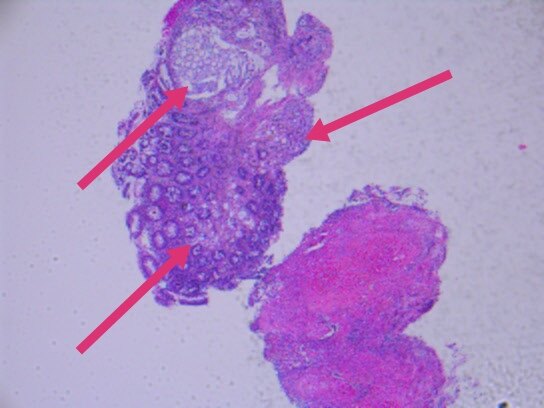

几天前,入我院行肠镜检查,并活检,显微镜下可见癌浸润于直肠粘膜之间。

最终,我们以上述HE形态为线索,老年男性,直肠占位,为XY坐标,我们初步音箱诊断就是前列腺腺泡腺癌浸润至前列腺腺外,累及直肠并形成肿块,浸润直肠全层至粘膜内。